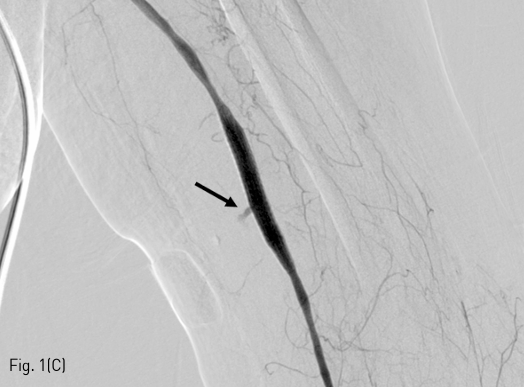

스텐트-크라프트 설치시 소량의 내강 유출이 있었으므로 주치의에게 위팔 부위의 부종이나 통증이 새로 생기거나 악화되면 다시 혈관 조영술을 시행할 수 있도록 주지하였다. 시술 1일 뒤에 시행한 상지 전산화단층촬영 혈관조영술에서 시술 부위에 특별한 이상이 없음을 확인하였다(Fig. 1D).

Fig 1D

(D) Computed tomographic angiography obtained one day after the procedure shows no further leakage or pseudoaneurysm. Small residual hematoma was noted around the puncture site (not shown).